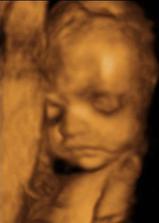

21.3. 4D ultrazvuk - neskutečně krááááásnýýýýýý.........za odměnu jsme pro mimi nakoupili skříně a další věci do pokojíčku